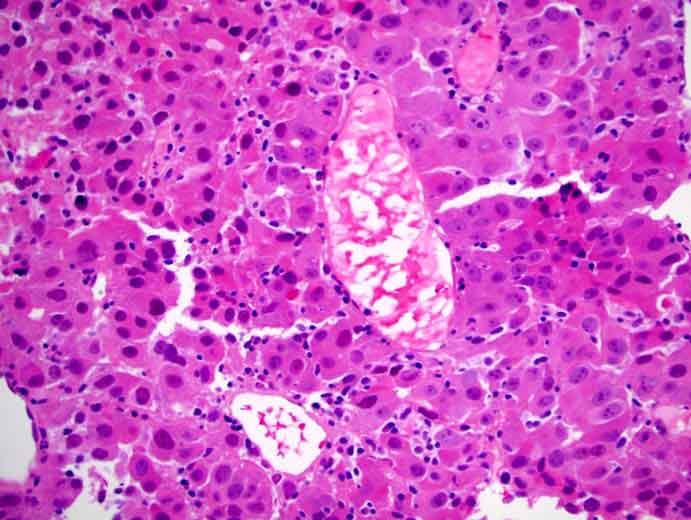

Ora, grazie a un crescente corpo di evidenze, i ricercatori britannici stanno valutando il loro utilizzo nel bersagliare le cellule tumorali e nell’attivazione di una risposta immunitaria nei confronti del cancro epatocellulare (HCC).

Questo tipo di patologia è una delle forme più comuni di cancro del fegato. In genere è causato dalla cirrosi epatica, per via dei danni che questa infonde all’organo.

«Il carcinoma epatocellulare, che comprende il 90 percento di tutti i tumori epatici primari, è una condizione estremamente difficile da trattare – spiega nel comunicato US il professore Khakoo – In questa prima fase dello studio ci proponiamo di creare un metodo per formare la base per una sperimentazione clinica nell’utilizzare le cellule NK per trattare l’HCC».